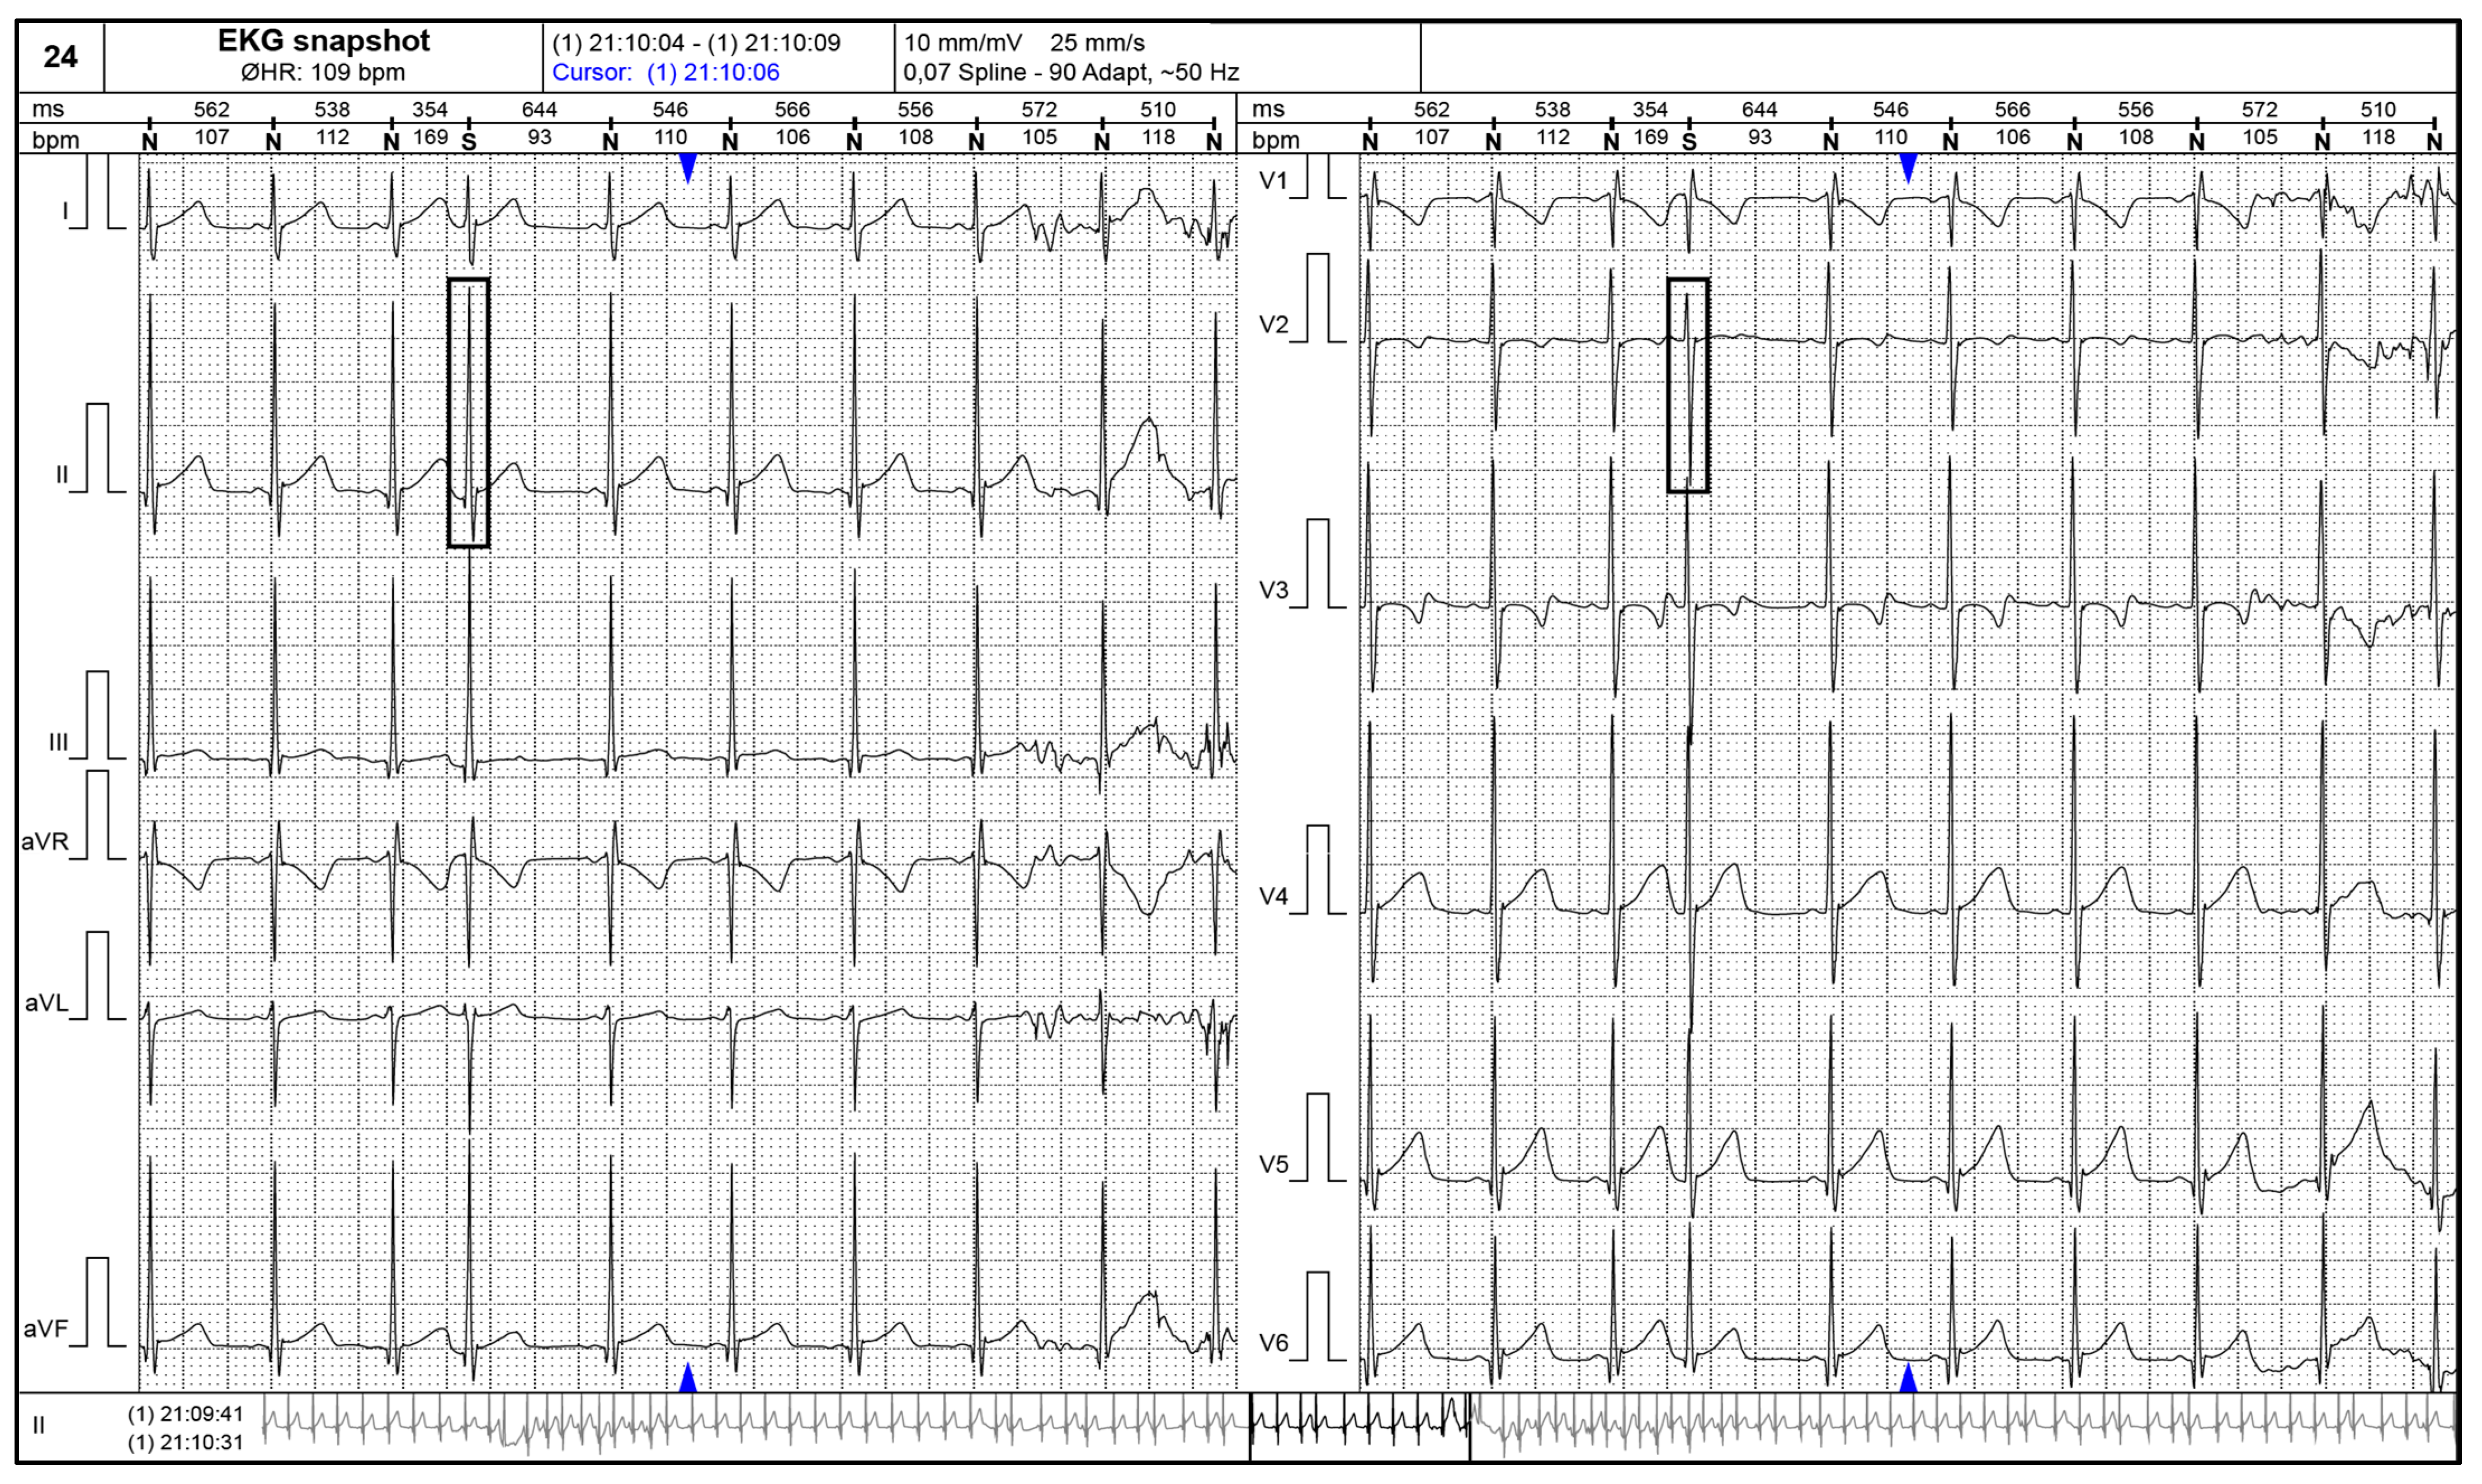

- Shiono, J.; Horigome, H.; Yasui, S.; Miyamoto, T.; Takahashi-Igari, M.; Iwasaki, N.; Matsui, A. Electrocardiographic changes in patients with cardiac rhabdomyomas associated with tuberous sclerosis. Cardiol. Young. 2003, 13, 258–263. [Google Scholar] [CrossRef] [PubMed]

- Aslan, E.; Sap, F.; Sert, A.; Odabas, D. Tuberous sclerosis and cardiac tumours: New electrocardiographic finding in an infant. Tex. Heart Inst. J. 2014, 41, 530–532. [Google Scholar] [CrossRef]

- Facin, M.; Pastore, C.A.; Samesima, N.; Pereira Filho, H.G. Ventricular repolarization abnormalities: The electrocardiographic track of cardiac tumoural involvement in an infant with tuberous sclerosis complex. A case report. Eur. Heart J. Case Rep. 2020, 4, 1–6. [Google Scholar] [CrossRef]

- Nguyen, T.; Smythe, J.; Baranchuk, A. Rhabdomyoma of the interventricular septum presenting as a Brugada phenocopy. Cardiol. Young 2011, 21, 591–594. [Google Scholar] [CrossRef] [PubMed]